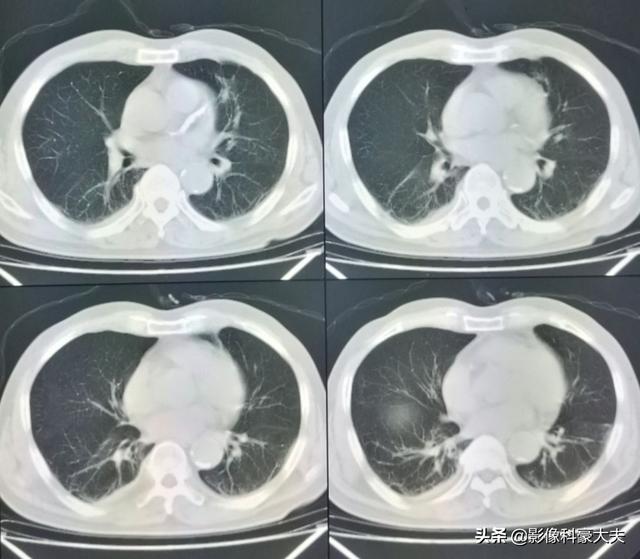

Ce nodule irrégulier dans le poumon gauche est le foyer principal, qui ne mesure que 2,6 cm. Un cancer du poumon avec des métastases osseuses comme celui-ci n'est plus opérable. On ne peut rien y faire, le cancer du poumon est trop fréquent et certains des premiers symptômes sont atypiques, voire asymptomatiques.Dans environ 30 % des cancers du poumon, les symptômes des métastases sont la première manifestation, et les métastases sont détectées en premier avant que d'autres cancers du poumon ne soient détectés.

Son examen tomodensitométrique le plus récent a montré que la photo primaire avait beaucoup rétréci et il a eu la chance de survivre avec une rétention pendant plus de 5 ans !